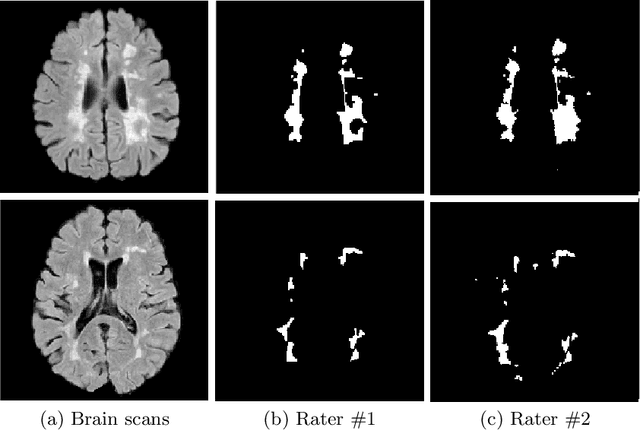

Abstract:The problem of inter-rater variability is often discussed in the context of manual labeling of medical images. It is assumed to be bypassed by automatic model-based approaches for image segmentation which are considered `objective', providing single, deterministic solutions. However, the emergence of data-driven approaches such as Deep Neural Networks (DNNs) and their application to supervised semantic segmentation - brought this issue of raters' disagreement back to the front-stage. In this paper, we highlight the issue of inter-rater bias as opposed to random inter-observer variability and demonstrate its influence on DNN training, leading to different segmentation results for the same input images. In fact, lower Dice scores are calculated if training and test segmentations are of different raters. Moreover, we demonstrate that inter-rater bias in the training examples is amplified when considering the segmentation predictions for the test data. We support our findings by showing that a classifier-DNN trained to distinguish between raters based on their manual annotations performs better when the automatic segmentation predictions rather than the raters' annotations were tested. For this study, we used the ISBI 2015 Multiple Sclerosis (MS) challenge dataset, which includes annotations by two raters with different levels of expertise. The results obtained allow us to underline a worrisome clinical implication of a DNN bias induced by an inter-rater bias during training. Specially, we show that the differences in MS-lesion load estimates increase when the volume calculations are done based on the DNNs' segmentation predictions instead of the manual annotations used for training.